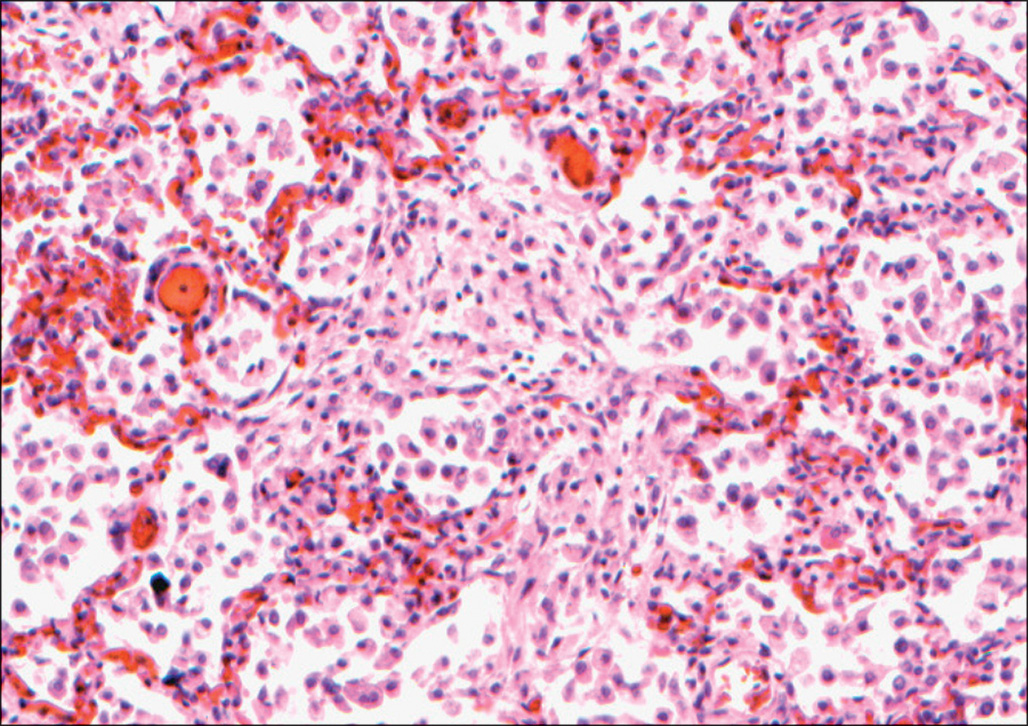

Once septicemia occurs, there is a generalized reaction that includes hypotension, tachycardia, increased hyperthermia or hypothermia, and poor perfusion of the intestines and other viscera. Coagulopathy is also an important complication of sepsis. In addition, once bacteria have gained entrance to the general circulation, tissue infection may develop at distant sites, particularly the lungs. One remarkable case demonstrated clearly the route of dissemination of fatal burn wound sepsis. The patient was admitted in a clinically septic condition 2 weeks after suffering a large burn but died in spite of aggressive therapy. At the time of autopsy there were many areas of bacterial proliferation within the burn wound, invasion of viable tissue deep to the burn eschar, and thrombosis of blood vessels invaded by bacteria at the margin of the necrotic zone. Bacteria were especially numerous within the smooth muscle of veins in the dermis. Lesions of ecthyma gangrenosum were not present in this case. Septic emboli with fibrous organization were seen in pulmonary artery branches in all lobes of the lungs. There were pale foci of necrosis throughout the lungs surrounded by hemorrhage filling the alveoli in a broad zone around each necrotic focus ( Fig. 38.3 ). Very little acute inflammatory reaction was seen in or around the many foci of bland necrosis in the lungs. In these necrotic foci, bacterial proliferation was very prominent within the walls of arteries. A direct hematogenous route of spread of infection from the skin to the lungs seemed clear in this case. Bacteria that had colonized the necrotic tissue associated with the burn wound, over time, apparently became more concentrated and extended into viable tissue, causing local necrosis. They became concentrated in the medial walls of veins at the border between necrotic and viable tissue, caused thrombosis of those vessels, and proceeded to extend into the fresh thrombi. Once the infected thrombi broke loose into the bloodstream, they naturally lodged in small pulmonary artery branches in the lungs, where they continued to grow and to become very prominent in the medial walls of the small pulmonary arterial branches.

In patients who have clinical evidence of sepsis at the time of death, extensive infection of the lungs is commonly present. Fatal pneumonia is most often seen as a consequence of infection with a highly antibiotic-resistant bacterial strain. Virulent and antibiotic-resistant strains of Pseudomonas or Acinetobacter may produce an angioinvasive infection in the lung, with massive proliferation of bacteria within the walls of pulmonary artery branches and necrosis of nodules of lung tissue in all lobes ( Figs. 38.3–38.5 ). This pattern is similar to that of ecthyma gangrenosum of the skin, which is also characterized by bland necrosis thought to be a result of ischemia. , A similar angioinvasive pattern of pulmonary infection can be seen with generalized infection caused by Aspergillus or similar filamentous fungi.

This micrograph, taken at low magnification, shows a small round pale area of necrotic lung tissue in which no nuclei are staining, surrounded by a zone of congestion and hemorrhage, with very little acute inflammatory reaction. H&E stain.

This high magnification micrograph shows numerous gram-negative rods within the wall of a small pulmonary artery branch and extending into the surrounding pulmonary interstitium. Tissue Gram stain.